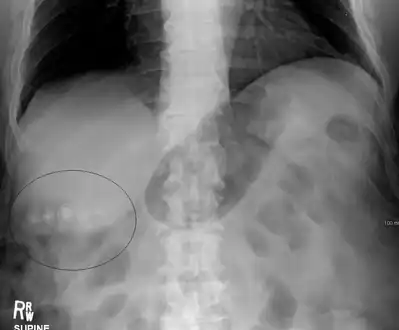

Mixed (brown pigment stones) typically contain 20–80% cholesterol (or 30–70%, according to the Japanese classification system).[38] Other common constituents are calcium carbonate, palmitate phosphate, bilirubin and other bile pigments (calcium bilirubinate, calcium palmitate and calcium stearate). Because of their calcium content, they are often radiographically visible. They typically arise secondary to infection of the biliary tract which results in the release of β-glucuronidase (by injured hepatocytes and bacteria) which hydrolyzes bilirubin glucuronides and increases the amount of unconjugated bilirubin in bile. Between 4% and 20% of stones are mixed.[3]

On abdominal ultrasound, sinking gallstones usually have posterior acoustic shadowing. In floating gallstones, reverberation echoes (or comet-tail artifact) is seen instead in a clinical condition called adenomyomatosis. Another sign is wall-echo-shadow (WES) triad (or double-arc shadow) which is also characteristic of gallstones.[40]

- A 1.9 cm gallstone impacted in the neck of the gallbladder and leading to cholecystitis as seen on ultrasound. There is 4 mm gall bladder wall thickening.

Biliary sludge and gallstones. There is borderline thickening of the gallbladder wall.- Gallstones as seen on plain X-ray